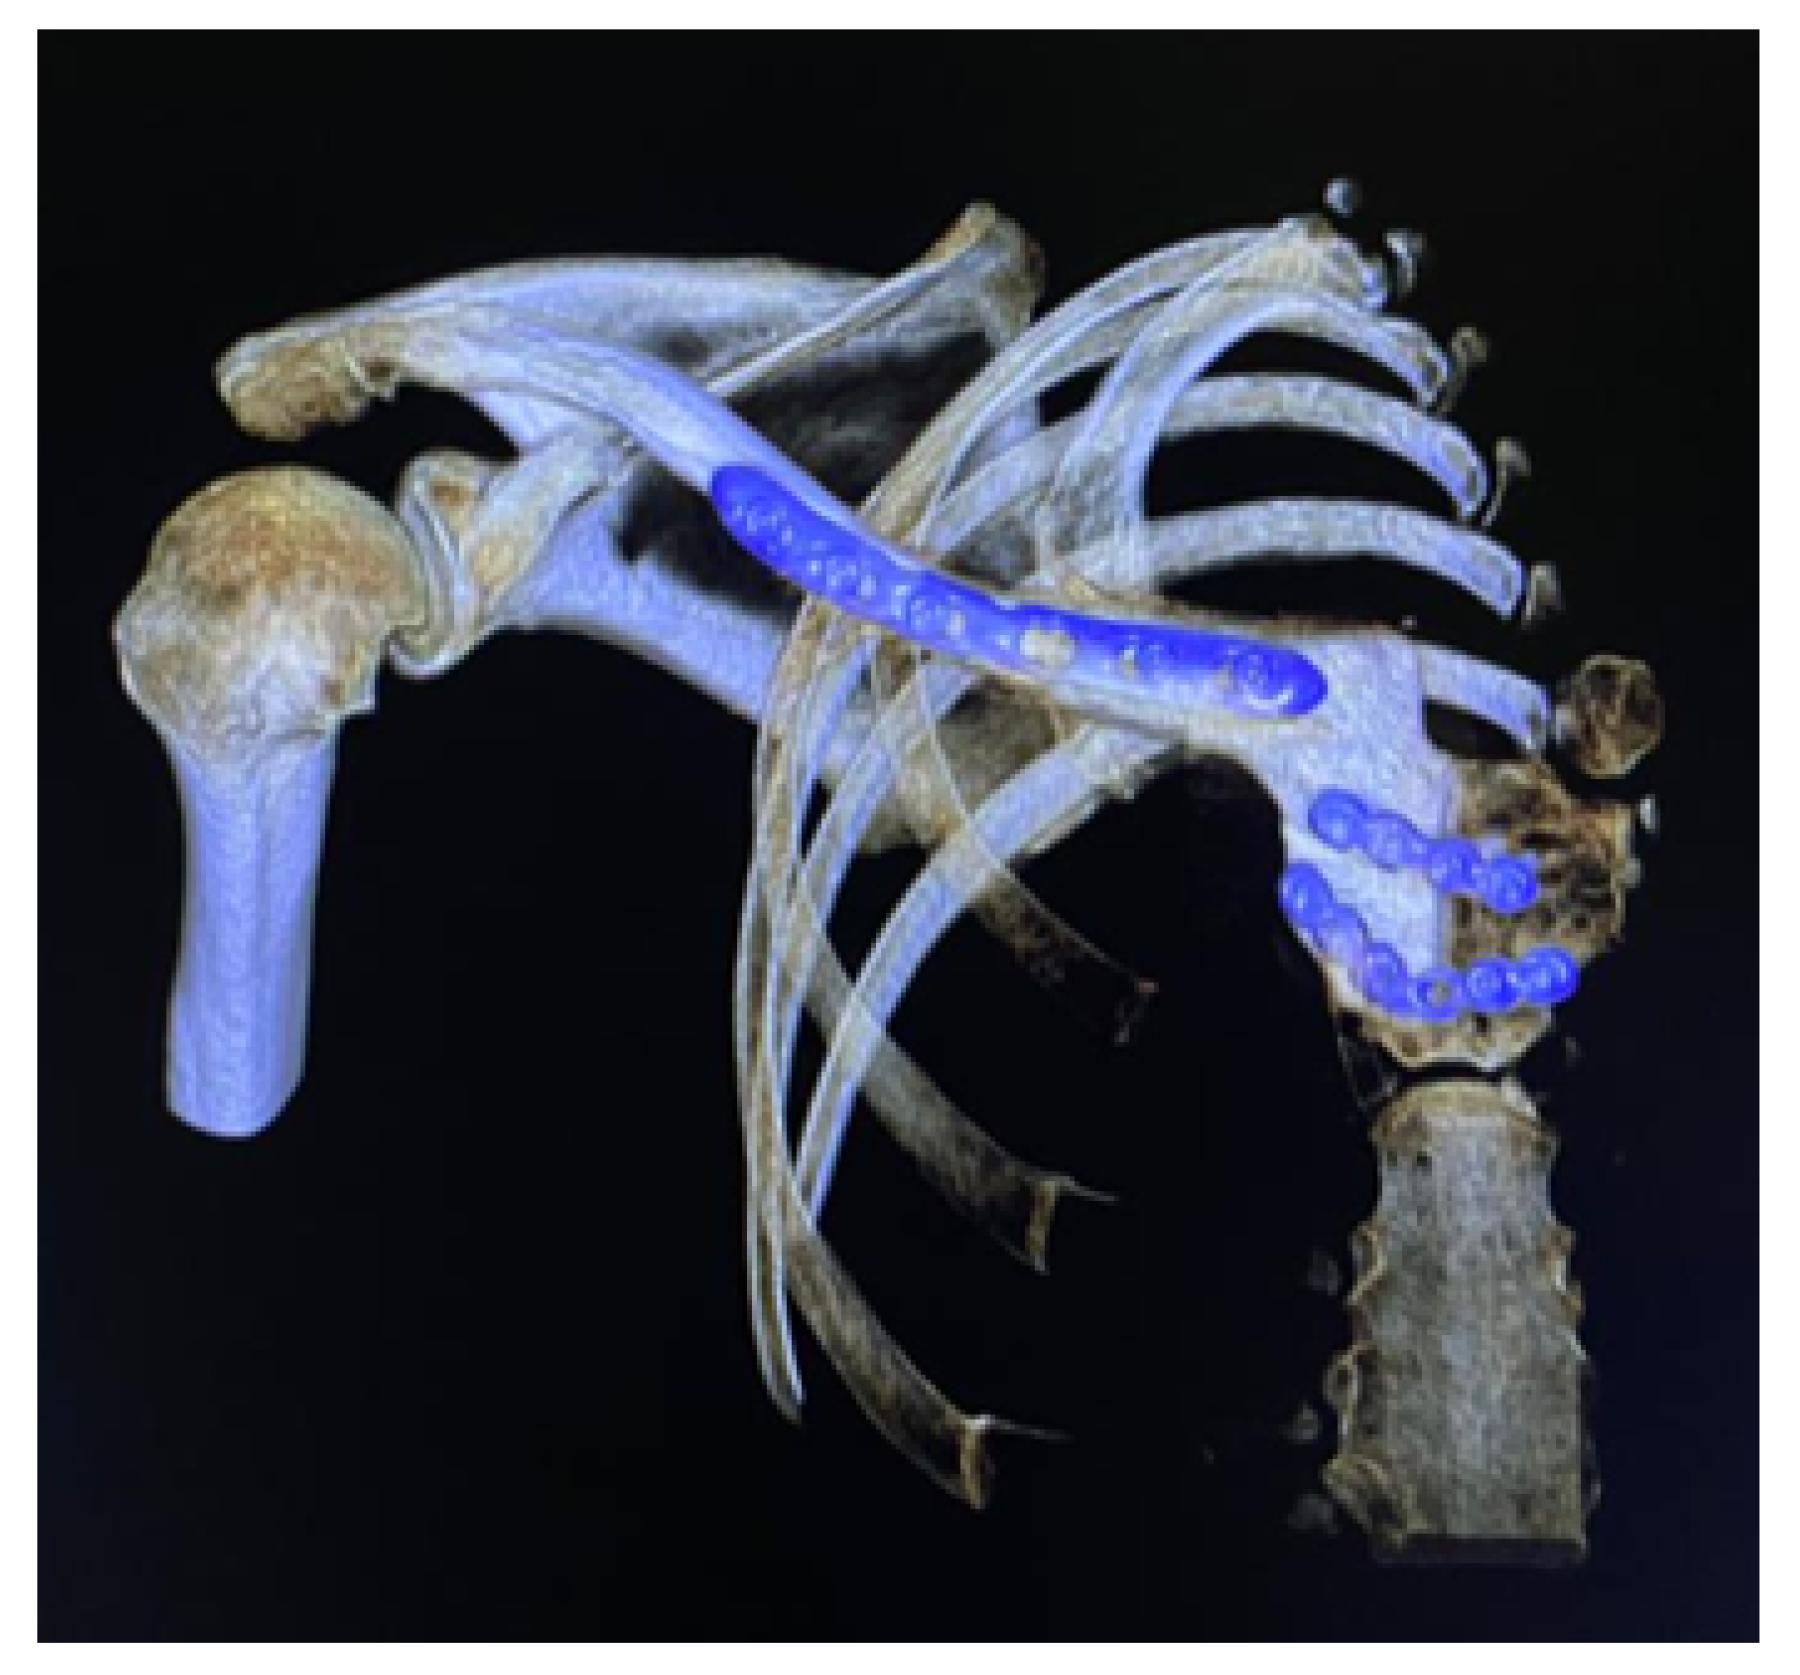

3.6. Case 6: Right Sternoclavicular Tumour

3.6.1. Diagnosis and Analysis

3.6.2. Surgical Planning

3.6.3. Design and Printing of Anatomical Models